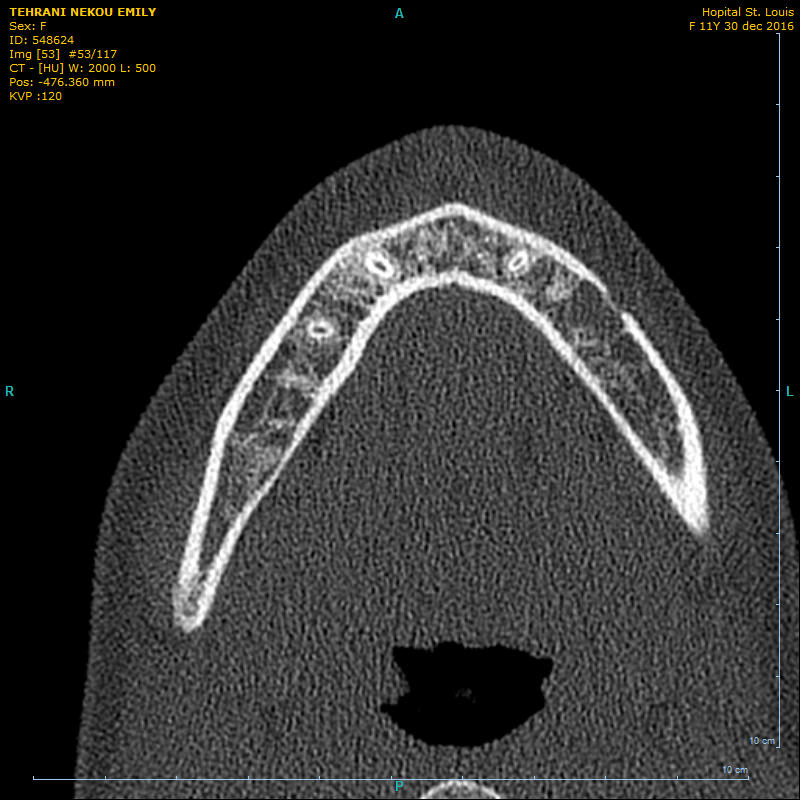

patiente de 11 ans. sans symptôme.au niveau de la 35 apicale, prédence d'une masse hétérogène. vitalité ok.

il n'y a pas de solution de continuité radiologique entre l'espace desmodontal et le périmètre de la lésion qui se superpose à la structure dentaire par un liseré dense.

Je ne crois pas du tout à une lacune de Stafne : trop antérieur et l'image scanner d'une lacune n'a rien à voir. Ca donne normalement une dépression de la table linguale de la mandibule en regard de la glande sous-maxillaire (donc normalement plus postérieur).